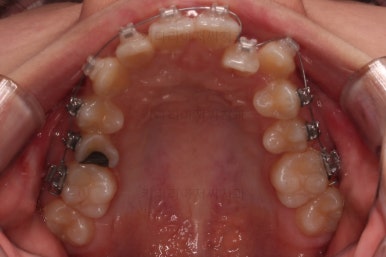

부산교정치료 초진 시 입안의 모습입니다.

치아가 전반적으로 삐뚤고, 덧니가 두드러져 보이네요.

그리고 선을 그려놨는데 윗니의 라인과 아랫니의 라인이 평행이 아니죠.

기울어 있어서 양측의 교합의 강도가 다른 상황이었습니다.

장치를 처음 부착한 사진입니다.

이번 환자분은 특징적으로 윗니의 장치와 아랫니의 장치가 다르죠.

윗니는 좀 더 심미적인 세라믹으로 선택하셨고 아랫니는 비교적 저렴하고 부피가 약간 작고 튼튼한 메탈로 진행했습니다.